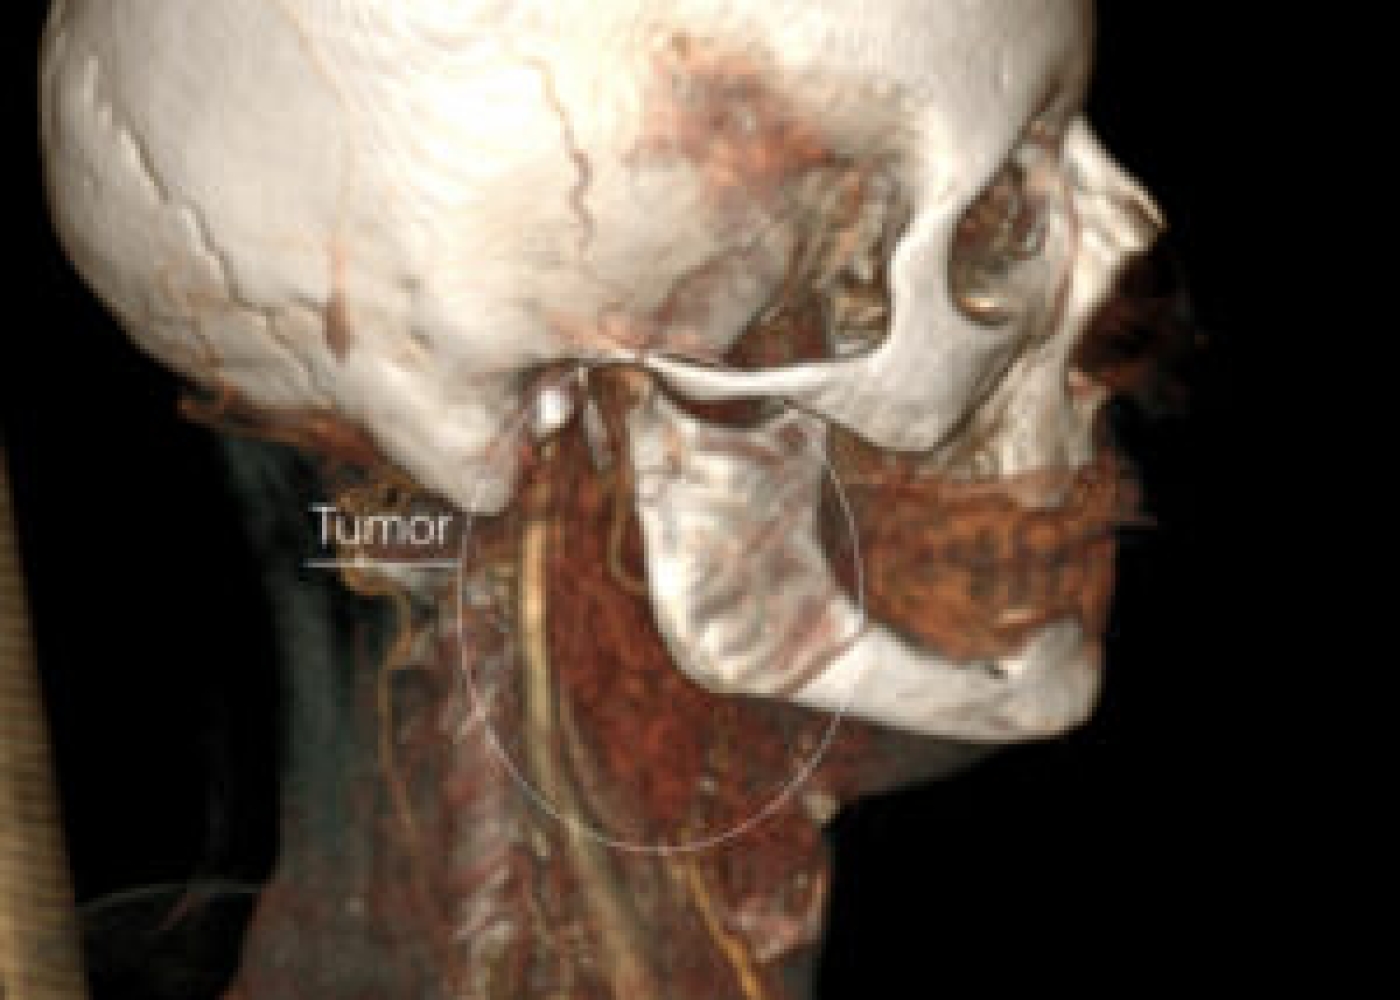

Պացիենտի խոսքով՝ գանգատներն ի հայտ են եկել մոտ 1,5 տարի առաջ և հաջորդիվ գոյացության չափերը զգալի մեծացել են: Հետազոտման ժամանակ աջից պարանոցի քնային եռանկյունում հայտնաբերվել է հստակ սահմաններով մոտ 4սմ տրամագծով անցավ գոյացություն:

Կլինիկոպարակլինիկական հետազոտությունների արդյունքում ախտորոշվել է քնային զարկերակի բիֆուրկացիայի անգիոմիոմատոզ համարտոմա աջից, որը ճնշում էր արտաքին քնային զարկերակը: